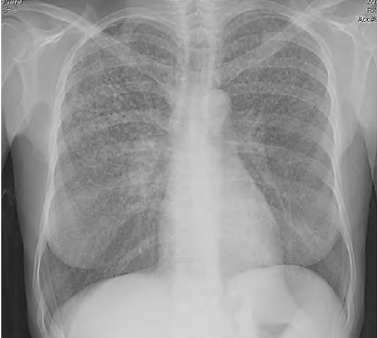

Uma paciente de 45 anos de idade compareceu, acompanhada pela filha, a uma consulta ambulatorial. Queixa-se de perda de peso (em torno de 4 kg nos últimos seis meses), febre vespertina e fadiga há mais de 20 dias. Observe que tem trabalhado muito, tem uma fadiga crônica e acha que iniciado os sintomas após exposição à chuva e o frio quando voltava do trabalho para casa. Ela informa que é etilista social e tabagista (15 cigarros / dia), e alguns exames laboratoriais como hemograma, eletrólitos, função hepática e renais normais. Os raios X de tórax estão representados na imagem a seguir. O resultado do PPD e o lavado brônquico são negativos.

Com base nesse caso clínico, na imagem apresentada e nos conhecimentos médicos correlatos, julgue o item a seguir.

A imagem dos raios X de tórax coloca a tuberculose como diagnóstico diferencial.